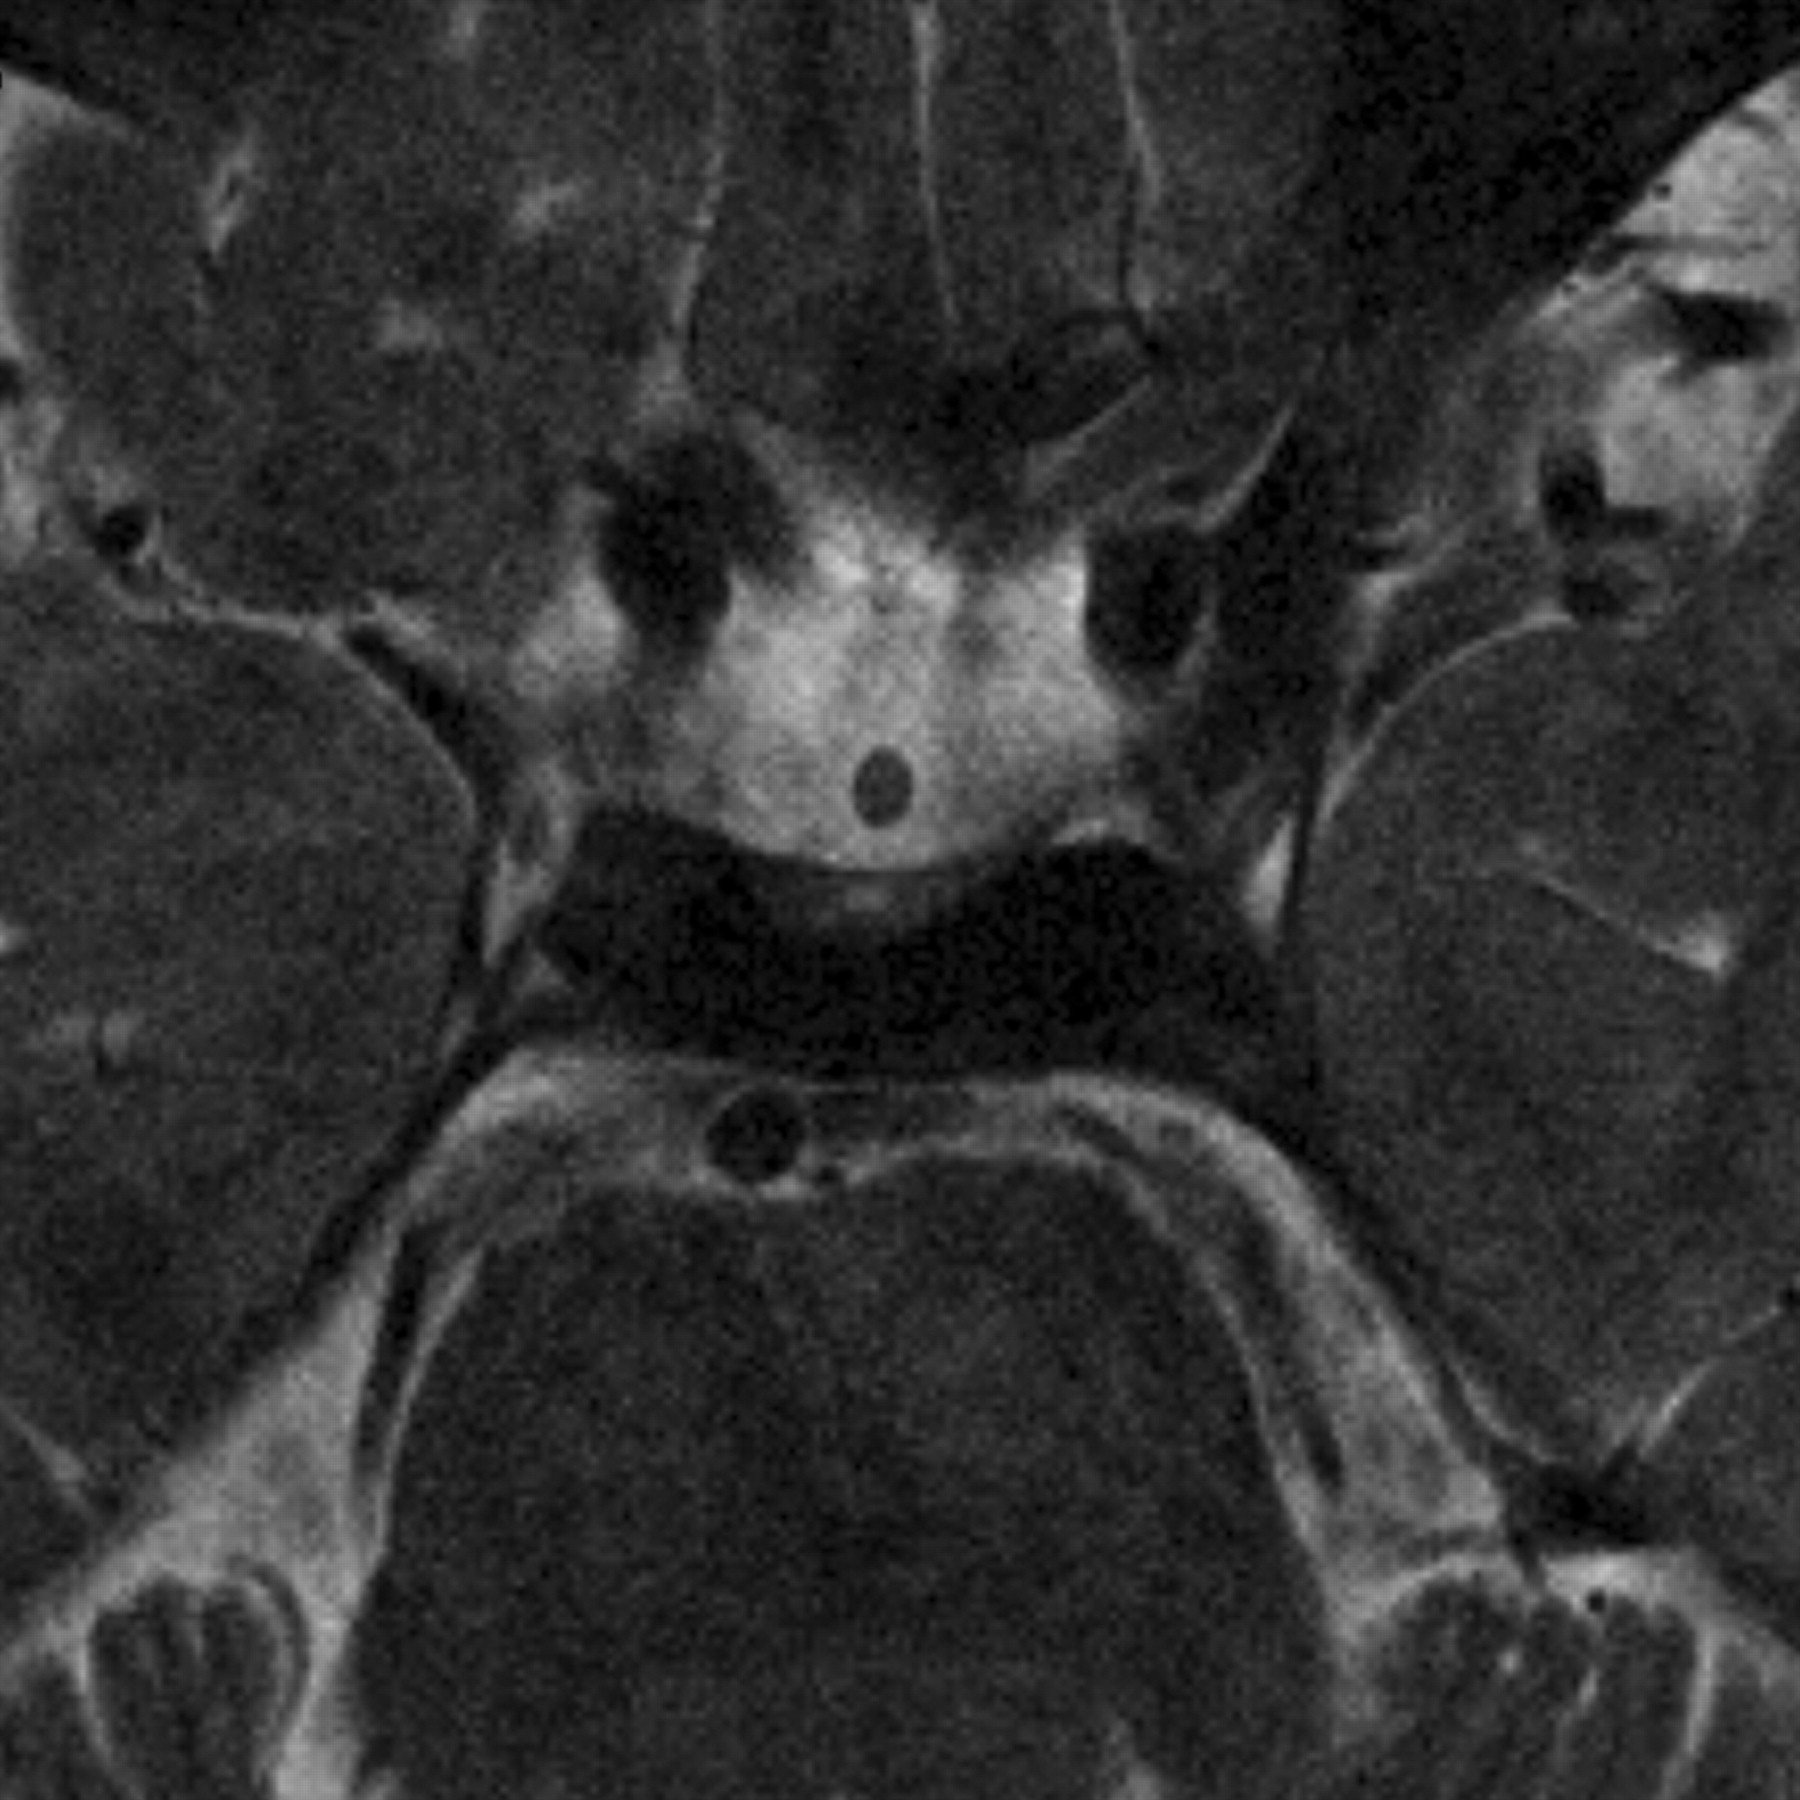

T2-weighted oblique-axial image of the pituitary stalk of a 34-year-old healthy man. The pituitary stalk shows homogeneous isointensity with the cerebral white matter at its insertion on the pituitary gland.